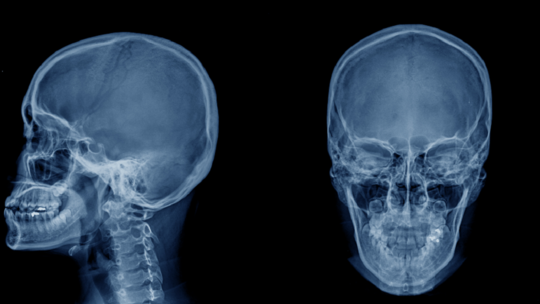

وجدت دراسة جديدة أن صدمة الرأس المتكررة ستجعل الجمجمة أكثر سمكا وكثافة - على الرغم من أن الباحثين غير متأكدين مما إذا كانت الجمجمة المدرعة توفر في الواقع أي حماية إضافية.

ووجد باحثون من جامعة موناش، في كلايتون أستراليا، أن الفئران التي لديها أوزان صغيرة سقطت على رؤوسها في محاولة لتحفيز أعراض الارتجاج، وجد أنها تتمتع بجماجم أكثر تقوية بعد شفائها.

ثم فحصت الفئران لقياس صحة الدماغ وكثافة العظام. وعثر على ارتباط واضح بين التأثيرات القاسية وسمك وكثافة جمجمة الشخص.